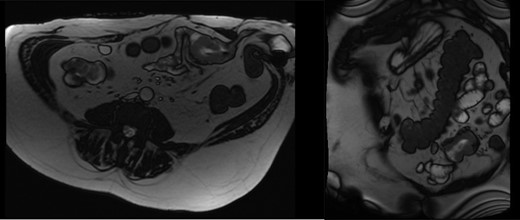

In 2017, repeat imaging showed resolution of all liver metastases, and the patient’s PSA was <0.1. While he had responded excellently to treatment, the patient had developed parastomal hernias around both the colostomy and ileal conduit. Between 2015 and 2017, the patient presented to hospital twice with features suggestive of small bowel obstruction. At the time, this was believed to be related to the hernias and therefore, the patient was planned for surgical repair of these hernias. During pre-operative workup, investigations revealed the patient to be anaemic with a haemoglobin of 80 and a ferritin of 11. Gastroscopy and colonoscopy revealed no abnormality; however, a pill cam demonstrated a single large lesion in the jejunum (Fig. 1). An MRI enterography was arranged to further characterize the lesion (Fig. 2). Given the excellent response to treatment, resolution of all liver metastasis and undetectable PSA levels a prostate cancer metastasis was not suspected. As the nature of this lesion was uncertain, a decision was made to perform a diagnostic laparotomy at time of hernia repair with small bowel resection if indicated.

The patient underwent a laparotomy, and a mass was discovered in the mid small bowel (Fig. 3). A small bowel resection was performed, followed by repair of both parastomal hernias with biological mesh. Histopathology showed poorly differentiated adenocarcinoma with positive Prostate-specific membrane antigen (PSMA) staining consistent with prostat cancer metastasis. The patient was referred to oncology for further treatment. On review two months later, the patient had recovered well from surgery with no signs of hernia recurrence.